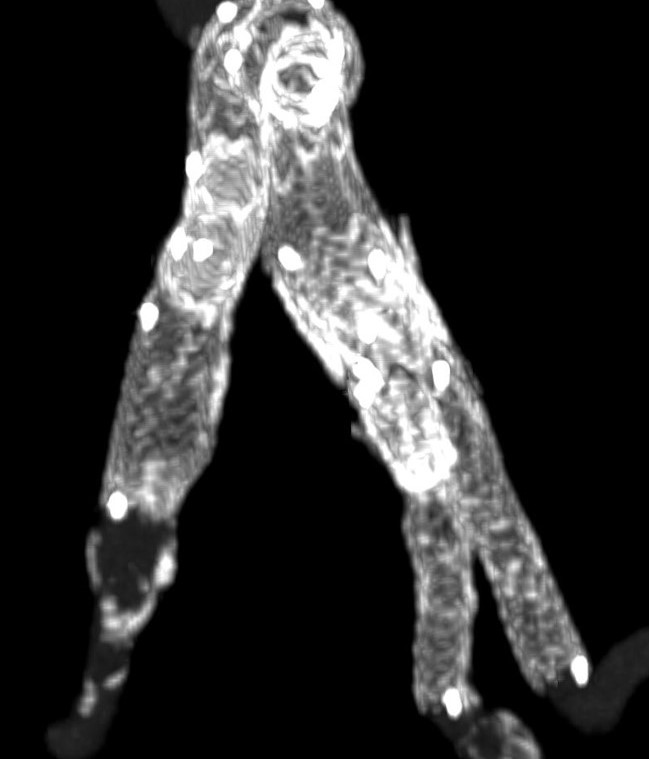

Άνδρας ασθενής 82 ετών με ανευρύσματα λαγονίων άμφω αριστερά διαμέτρου 4,1 εκατοστών και δεξιά διαμέτρου 5,1 εκατοστών, χωρίς συμμετοχή της κοιλιακής αορτής

Αντιμετωπίστηκε ενδαγγειακά με τοποθέτηση μοσχεύματος τύπου Zenith και δύο λαγόνιες προεκτάσεις με πλάγιο κλάδο για διάσωση και των δύο έσω λαγονίων αρτηριών